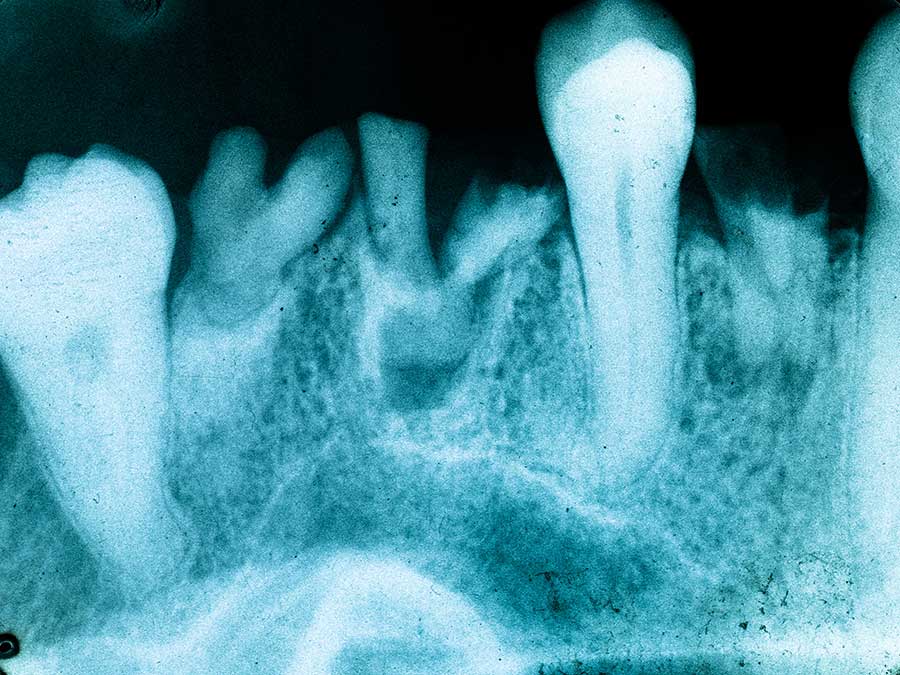

Accurate diagnosis is essential for effective treatment planning in oral pathology. Modern diagnostic tools like biopsies, imaging techniques, and laboratory tests play crucial roles in identifying the specific cause of oral lesions or diseases. Biopsies involve removing a small tissue sample for microscopic examination, helping to determine the nature of the lesion. Imaging techniques, such as X-rays and CT scans, can reveal underlying structures, identifying potential abnormalities or bone loss. Laboratory tests, such as blood tests and cytology, assist in evaluating systemic factors that might contribute to oral conditions. Precise diagnoses enable clinicians to implement targeted treatment plans.